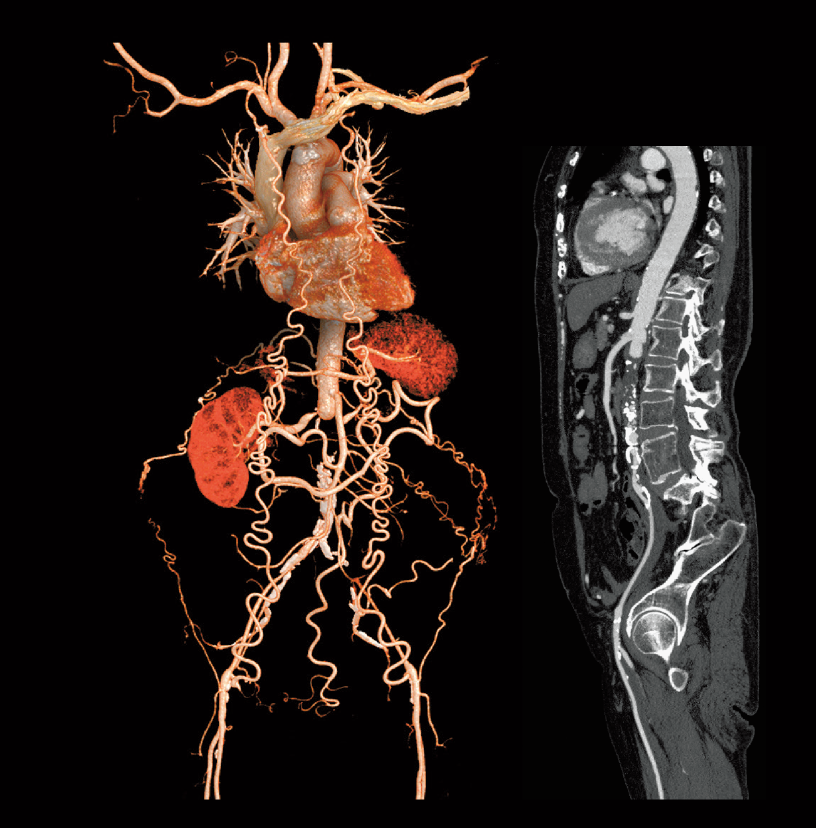

Carcinoma de células renales (80 kV)